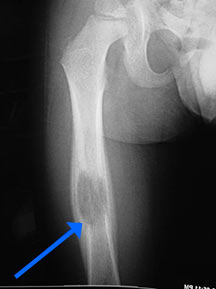

- • The work-up often consists of a physical examination, X-rays, CT scans, MRI, and sometimes bone scans are required.

Radiographic imaging is used to help form a diagnosis. These include X-Ray, MRI, CT and Bone Scans.

An example of an Eosinophilic Granuloma MRI is shown.